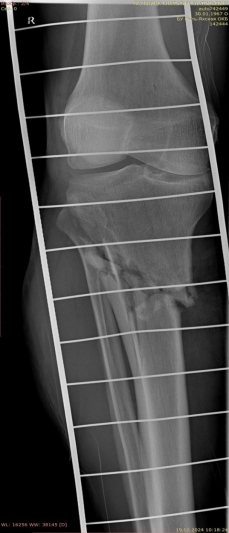

3) Мужчина, 52 года. Производственная травма в результате падения трубы с высоты двух метров на область голени. Открытый оскольчатый перелом большеберцовой и малоберцовой костей правой голени в средней трети со смещением отломков. Обширная рвано-ушибленная рана правой голени с дефектом мягких тканей (рис. 7).

Рис. 7.